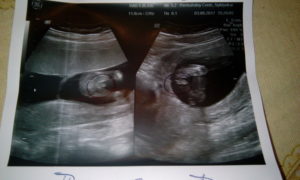

На фото Узи на 15 неделе беременности можно увидеть, как плод активно развивается и становится похожим на маленького человека, своими успехами радуя будущую маму

Что видно на фото плода?

На фото становится отчетливо видно, что плод похож на обычного крохотного ребёнка. Чётко просматриваются ручки и ножки.

Фото УЗИ размера плода на 15 неделе беременности

Возможность сделать фото УЗИ размеров плода на 15 неделе беременности — это уникальный шанс увидеть своего малыша на самой ранней стадии развития.